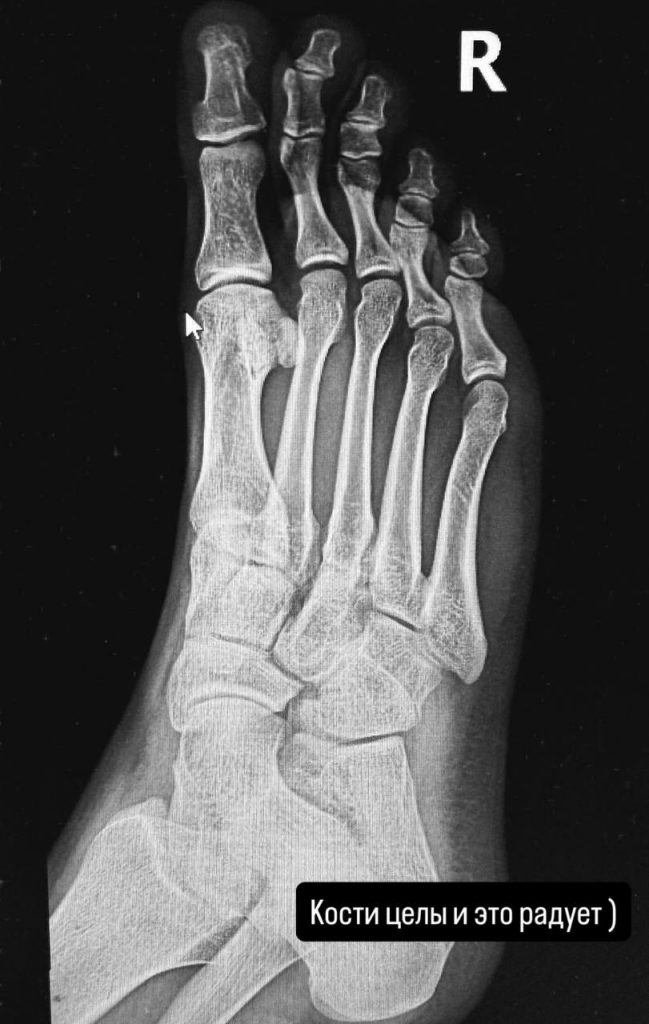

31-летний музыкант опубликовал фото из клиники, где он сидит в инвалидном кресле, нога плотно забинтована, а в руках держит кроссовок. В подписи Егор назвал произошедшее «небольшими приключениями перед полетом» и признался, что ему повезло: кости не пострадали.

Позже исполнитель записал видеообращение для поклонников, где поблагодарил всех за поддержку и сообщил, что уже на пути в Москву: «Друзья, спасибо всем кто переживает и желает скорейшего выздоровления. Дохромал до самолета, вылетаем в Москву, все нормально. Чуть-чуть похромаю и все обязательно пройдет. Главное, что кости целы».